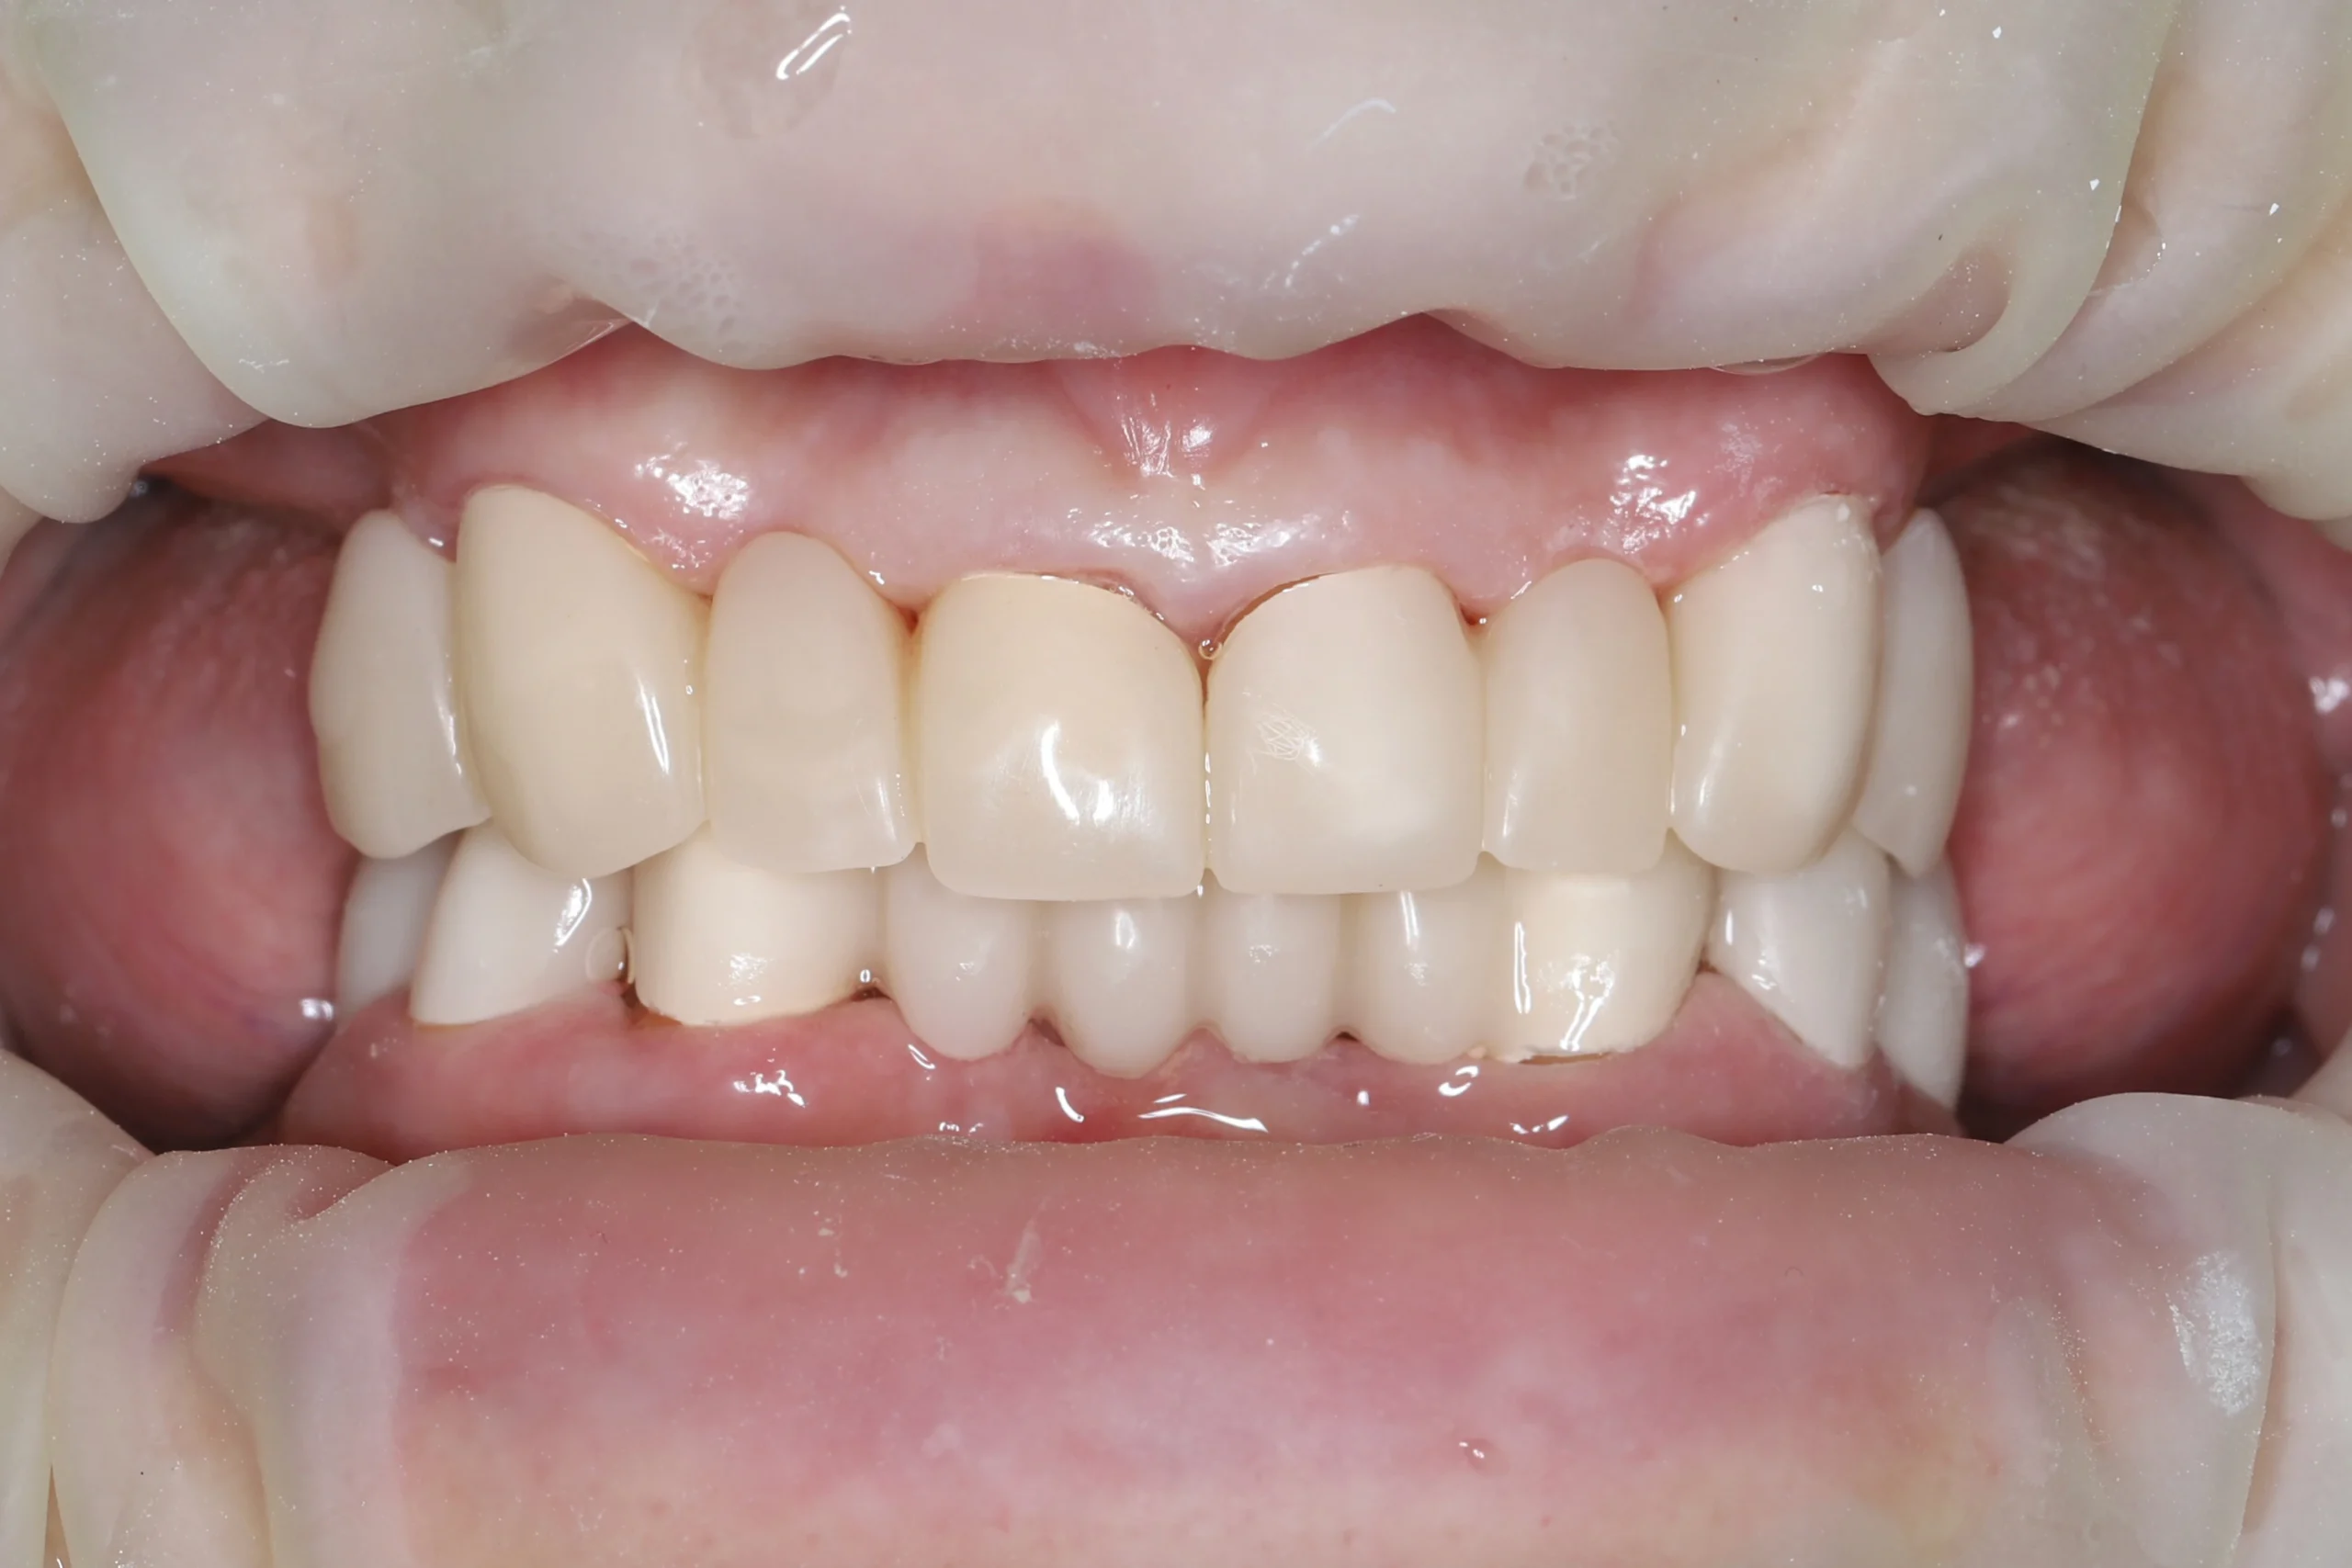

На основе цифровых оттисков в лаборатории изготовили PMMA-коронки (промежуточные между временными клиническими и постоянными). Они обеспечили стабилизацию прикуса, восстановление и адаптацию слизистой полости рта перед имплантацией.

Открытый кюретаж

Также с целью улучшения состояния дёсен, уменьшения глубины пародонтальных карманов и выраженности воспаления пациентке выполнили открытый кюретаж. В результате сформировался стабильный контур дёсен: они стали бледно-розовыми, плотными, без кровоточивости. Исчез галитоз — неприятный запах изо рта.

Текущий статус

Пациентка ходит с PMMA-коронками, окклюзия стабильна, слизистая без признаков воспаления. Через 3–4 месяца после имплантации планируется финальный этап — протезирование постоянными конструкциями.

Результаты на этом этапе:

- Восстановлены жевательная функция и эстетика улыбки

- Стабилизированы контур дёсен и состояние пародонта

- Пациентка комфортно адаптировалась к временным реставрациям и отмечает улучшение дикции и уверенности при общении.